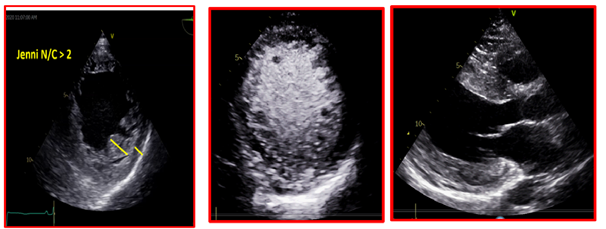

She provided a history of atypical chest pain, exertional shortness of breath, and occasional palpitation on further assessment—no lower limbs edema or syncope. Physical examination was utterly unremarkable. ECG (Figure 1) revealed brad ectopic pacemaker rhythm in lower atrial focus, Q waves in inferior leads with R wave in V1-V2, and nonspecific ST-T changes. Transthoracic echocardiography with contrast (TTE) revealed a thickened LV with more than three trabeculations protruding from the posterolateral wall. These moved synchronously with the myocardium (Figure 2). Intertrabecular recesses were evident, and the systolic function was moderately reduced (LV ejection fraction, 0.37), with a thick basal-mid septum of 1.9cm. The rest of the LV wall is hyper-trabeculated (Figure 2). Cardiac MRI showed thick basal-mid septum (1.9cm), hyper trabeculated LV with Peterson et al. criteria of 2.5 in keeping morphically with the diagnosis of LVNC. A patchy diffused mid-wall myocardial enhancement from base to apex was noticed indicates myocardial fibrosis. No cardiac thrombi were appreciated (Figure 3).

Figure 2 TTE revealed a thickened LV with more than three trabeculations protruding from the posterolateral wall. These moved synchronously with the myocardium. Intertrabecular recesses were evident.

24-hour Holter monitor records NSVT, high burden PVCs (17%), multiple PVCs morphology, and non-sustained run of atrial ectopy. Jenni’s criteria diagnosed LVNC; the ratio of non-compacted NC to compacted C layer in systole is 2.1 (Yanni et al.) and MRI Peterson criteria.8,9

Cardiomyopathy has different etiologies, with LVNC being one of the uncommon causes. It is characterized by prominent trabeculations and intertrabecular recesses that communicate within the ventricular cavity.11,12 The condition affects the LV; however, it might also be biventricular. It is assumed to be caused by the arrested development of the myocardial compaction between weeks five and eight of the embryogenesis.13 The most frequently affected myocardial segments are the apex, the distal, and the middle segments of the inferior and lateral walls. The affected segments have a 2-layered structure: a thin compacted pericardial layer and a thicker noncompacted endocardial layer with deep recesses— the basis of the LV noncompaction definition (Figure 2).14